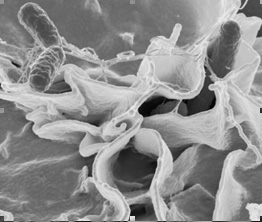

وهناك عديد من الأمراض تحدث من عدة أنواع بكتيرية لعل أكثرها شيوعاً:

Campylobacter:

تشتمل الأعراض على تقلصات فى المعدة وإسهال حاد ونادراً مايحدث قئ. ويمكن أن يبدأ هذا بعد من 2-10 أيام من تناول الطعام الملوث ولكنه عادة مايستغرق الأمر 2-5 أيام. والمصدر الرئيسى للتلوث بها هى الدواجن واللحوم غير تامة النضج under cooked، مداعبة الحيوانات والتعامل معها handling pets، التلوث من طعام آخر ملوث Cross contamination، اللبن الخام والمياه الملوثة. وهذا الميكروب Campylobacter هو السبب الأكثر شيوعاً للإسهال الحاد الذى يصيب الكبار.